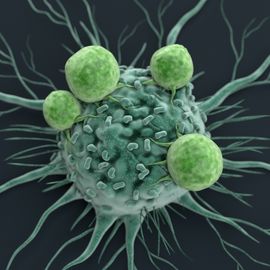

抗癌治疗

这个页面提供了教育资源、事件、新闻和产品相关抗癌疗法。内容将涵盖方面,从化疗和放射治疗,细胞治疗和癌症疫苗。

癌症免疫学

这个页面提供了教育资源、事件、新闻和产品相关的癌症免疫学。内容将涵盖从肿瘤免疫微环境和免疫监视方面,癌症免疫疗法和疫苗。